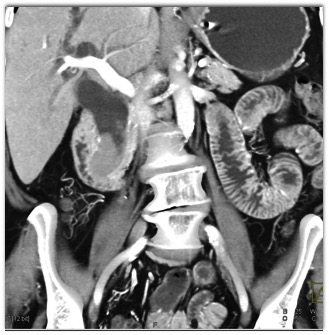

The best diagnosis of this patient with new onset jaundice includes all of the following except for?

biliary adenoma

non opaque stone or sludge

distal CBD adenocarcinoma

choledochal cyst